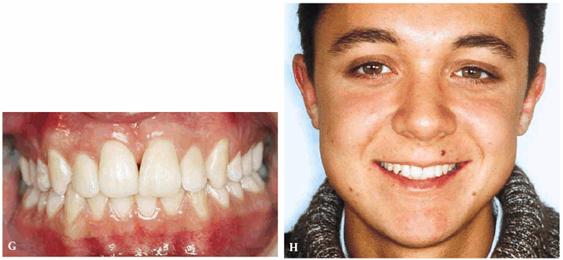

From an orthodontic perspective, a serious skeletal Class II with deep bite is becoming more and more evident. Therefore, orthodontic treatment has been initiated in both arches to align the dentition over the basal bone in harmony with the surrounding hard and soft tissues, as well as to achieve good esthetics (Figures 27-7F and G

Figure 27-7F and G: The same patient during the orthodontic treatment and after. Good esthetics has been achieved.